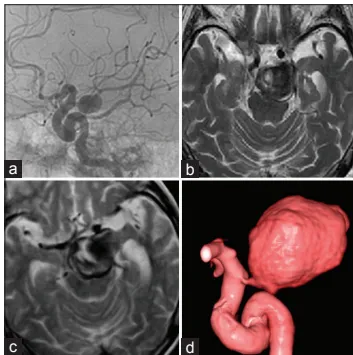

(a)确诊后4个月的血管造影显示,动脉瘤直径为12mm,起源于后交通动脉。

(b)确诊后2年3个月的磁共振成像(MRI)显示,动脉瘤伴血栓形成,直径增大至30mm,且压迫脑干。

(c)、(d)(确诊后)再经6个月,磁共振成像(c)及三维计算机断层扫描血管造影(3D-CTA,d)显示,病灶进一步扩大,直径达35mm;动脉瘤从后交通动脉向上方扩张,右侧大脑后动脉未显影。